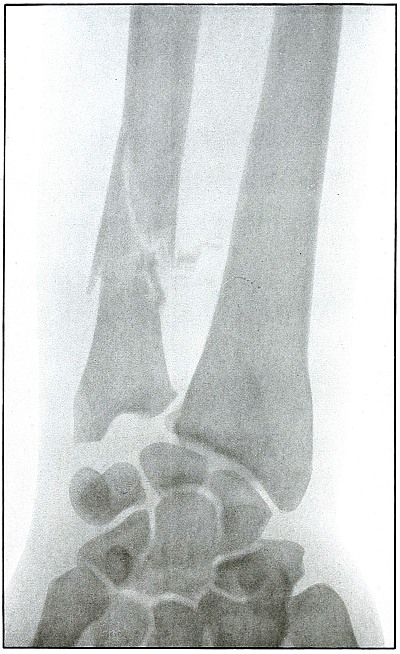

Plate 61.

_

[Pg 133]

Rifle—Plate 61.

LOWER EXTREMITY.

Gunshot Fracture of the Lower Ends of the Tibia and Fibula.

The course of the bullet was transverse, with the velocity of mid-range.

The fragmentation of the fibula, lying close to the skin, would produce considerable laceration in the wound of exit.

The treatment is conservative. Infection would depend almost entirely upon the integrity of the first dressings and immobilization.

Results should be favorable, with care in subsequent treatment. [Pg 134]